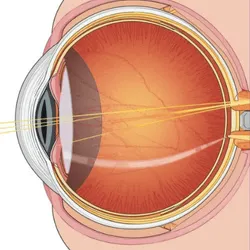

A squint, medically known as strabismus, is a condition where the eyes are not aligned properly. In this situation, one eye may turn inward, outward, upward, or downward while the other eye remains focused on a single point. This misalignment can be constant or may occur intermittently. The problem arises because the extraocular muscles, which control eye and eyelid movement, do not function in coordination. As a result, both eyes fail to focus on the same object at the same time. To correct this misalignment and restore proper alignment, surgical treatment is often recommended as an effective solution.

Eyeglasses or contact Lenses

These are commonly used by individuals with uncorrected vision problems. By wearing corrective lenses, the eyes don’t need to strain as much to focus, which helps them remain properly aligned.

Prism Lenses

These special lenses guide light correctly into the eye, improving focus and reducing unnecessary eye movement. By minimizing the effort required to align vision, they help the eyes work more comfortably and efficiently when looking at different objects.

Eye muscle surgery

Surgical treatment involves altering the length or strength of the eye muscles to achieve proper alignment. It is done under general anesthesia, with dissolvable stitches. In some adults, adjustable strabismus surgery is offered, allowing post-surgery fine-tuning of muscle positioning.